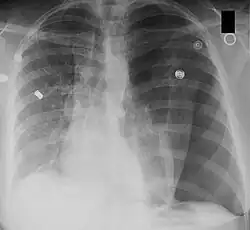

| Left tension pneumothorax with a large, well-demarcated area devoid of lung markings with tracheal deviation and movement of the heart away from the affected side. |

Tension pneumothorax

Tension pneumothorax is an emergent condition in which air gets trapped in the space between the chest wall and the lung. This space is referred to as the pleural space. Because air can't escape from this space, the air pocket grows larger and larger, resulting in the lung collapse closest to the pneumothorax. Forces are transmitted to the mediastinum and effectively "push" the mediastinal structures to the opposite side of the chest.[5]